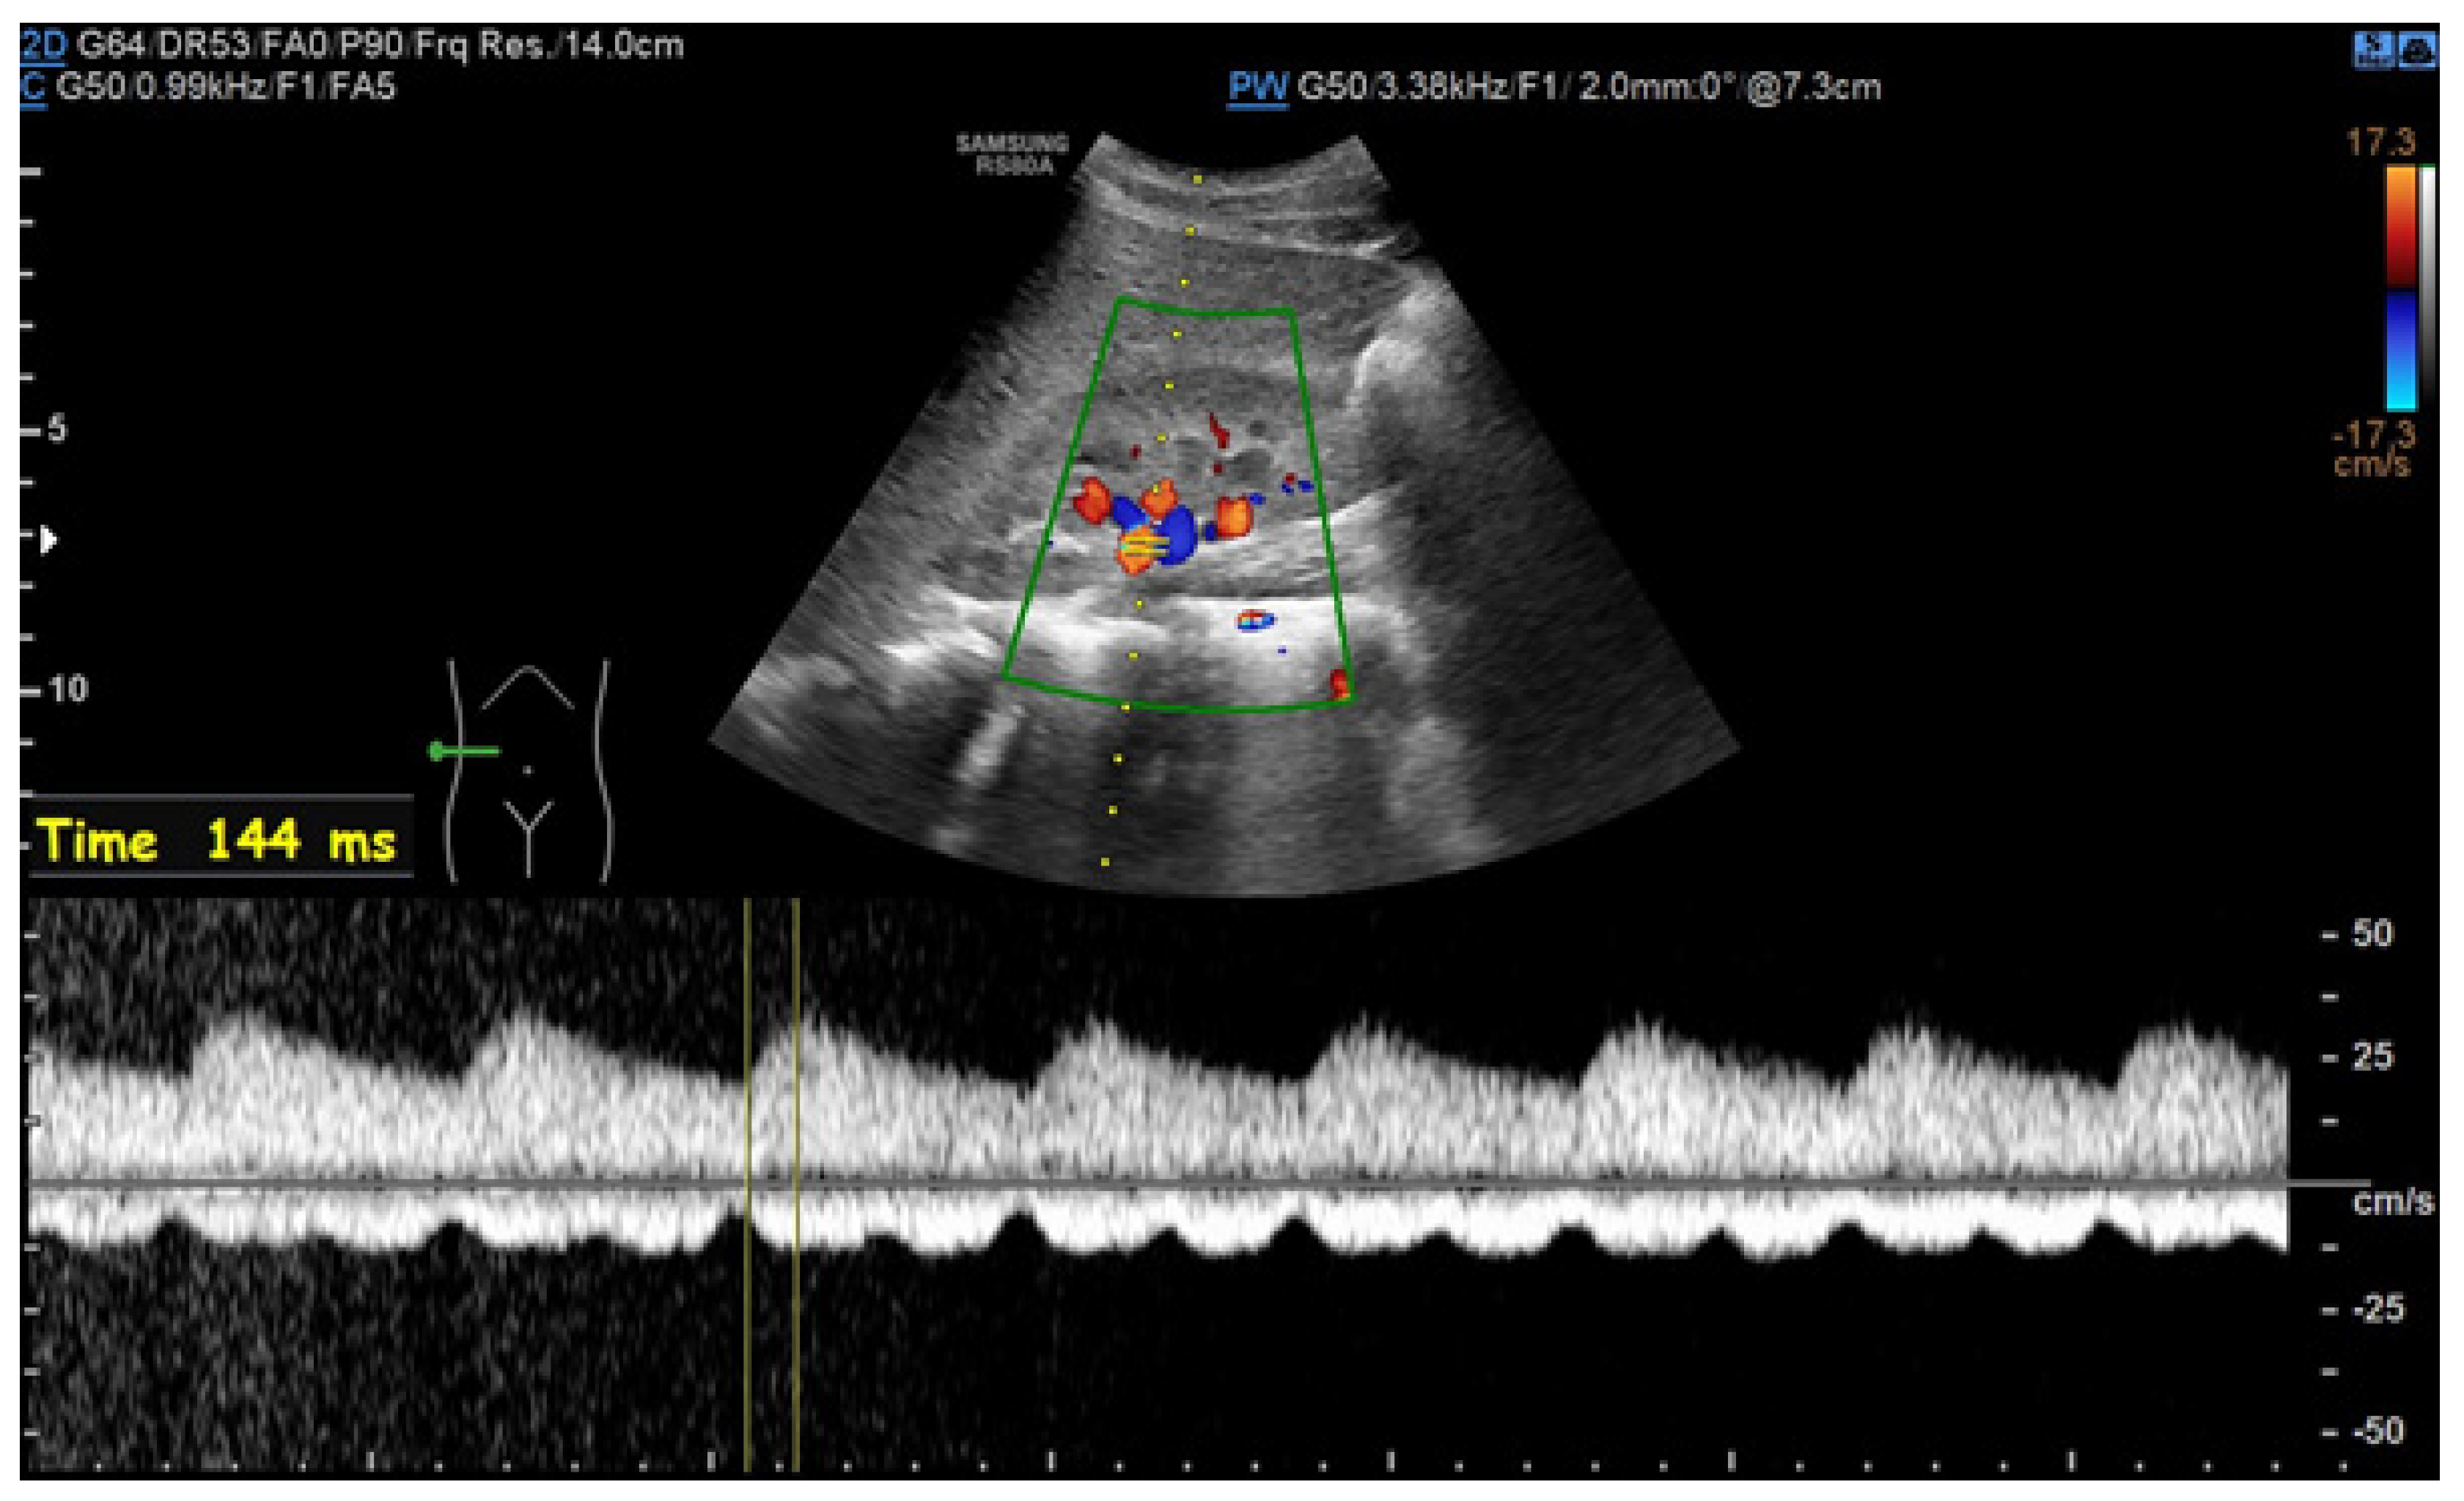

6.1. Ultrasound

- Drelich-Zbroja, A. Polish Society of Ultrasonography Standards—Update: Ultrasound Examination of Renal Arteries. J. Ultrason. 2014, 14, 297–305. [Google Scholar] [CrossRef]

- Stryczyński, Ł. Doppler ultrasound of renal arteries. Arter. Hypertens. Pract. 2022, 8, 186–199. [Google Scholar]

| Normal Value | Parameter |

|---|---|

| 100 cm/s * | PSV (peak systolic velocity) in artery trunk |

| 0.8–1.0 | RAR (renal aortic ratio) in artery trunk |

| ≤70 ms | AT (acceleration time) in intrarenal branches |

| 0.5–0.8 | RI (resistance index) in intrarenal branches |

| 0.78–1.33 | PI (pulsatility index) in intrarenal branches |

| >3 m/s2 | AI (acceleration index) in intrarenal branches |